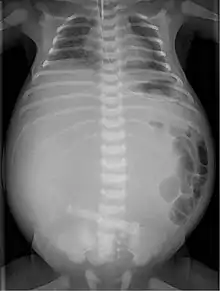

| Radiograph with double bubble sign indicating duodenal atresia | |

If not diagnosed in utero, infants with intestinal atresia are typically diagnosed at day 1 or day 2 after presenting with eating problems, vomiting, and/or failure to have a bowel movement.[3] Diagnosis can be confirmed with an X-ray, and typically followed with an upper gastrointestinal series, lower gastrointestinal series, and ultrasound.[5][3]